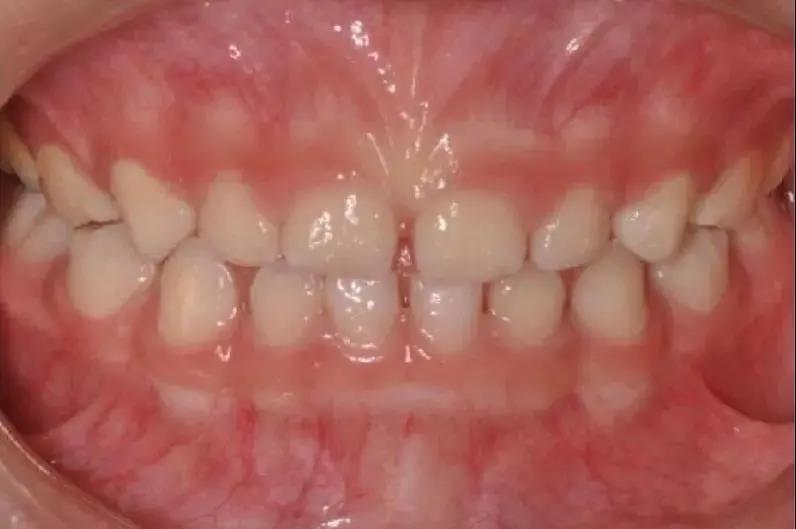

如發(fā)現(xiàn)孩子上下頜骨位置不佳

比如有明顯“齙牙”,應盡早矯治

早期矯治可以充分利用兒童的頜骨發(fā)育潛能

調(diào)整頜骨的生長平衡及牙弓發(fā)育

因此齙牙還是要盡早診治哦